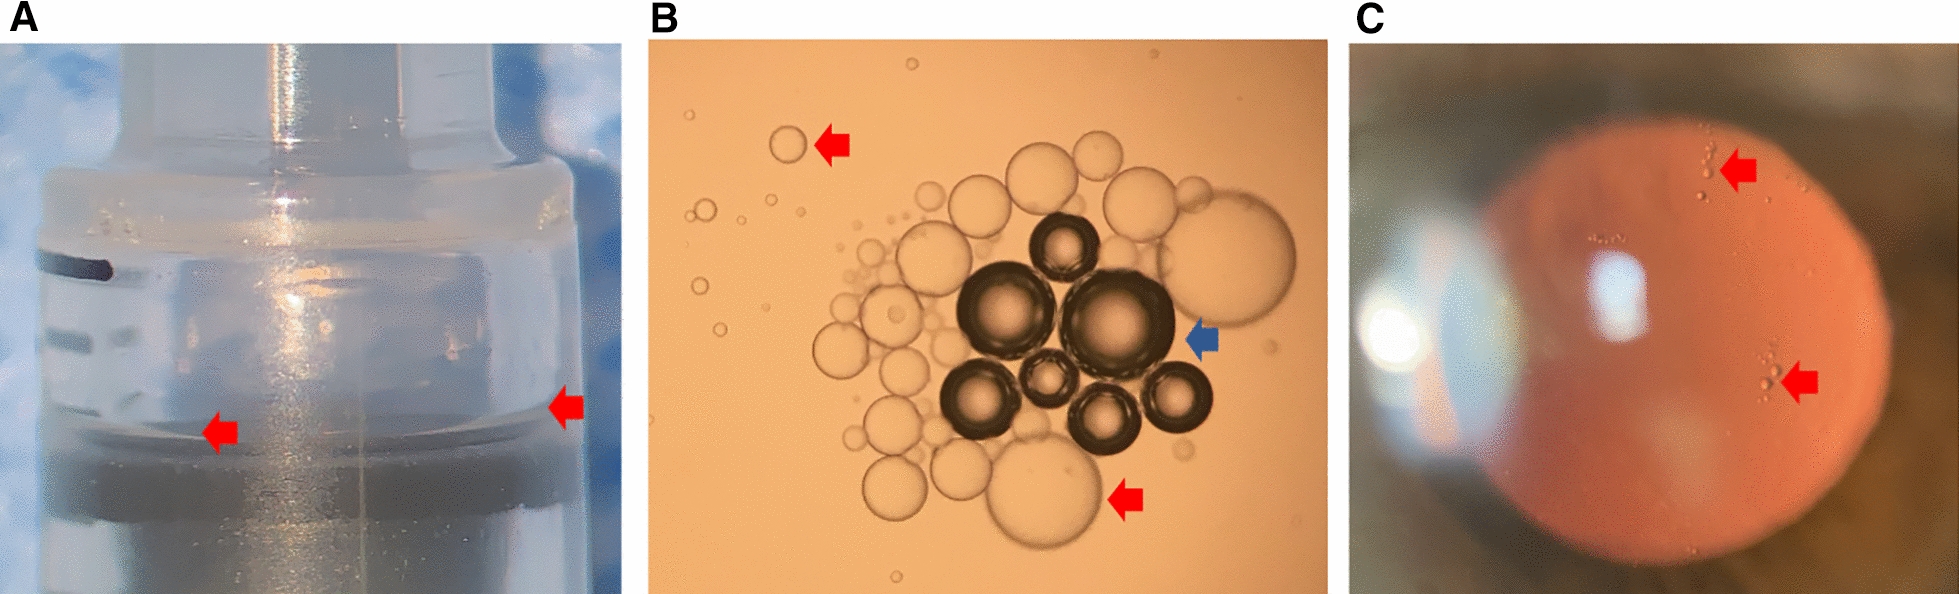

Fig. 1.

Illustrative images of silicone oil from the syringe. A Silicone oil layer (red arrowhead) in the barrel of the syringe adjacent to the rubber stopper. B Multiple silicone oil droplets (red arrowhead) seen at light microscopy released from the syringe. Note the presence of air bubbles (blue arrowhead). C Silicone oil droplets (red arrowhead) in the anterior vitreous of a patient who had recently recovered from non-infectious endophthalmitis following intravitreal injection of an antiangiogenic drug